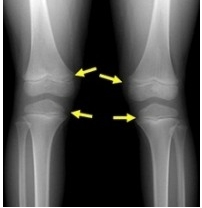

뼈에서 길이가 자라는 부분을 성장판이라고 하는데요. 요즘 부모님들 관심사 중 하나입니다. 우리 아이가 나보다 더 컸으면 하는 맘인데 성장판이 닫혔다고 하면 눈앞이 깜깜해집니다. 하지만 방법이 있습니다.

성장판이 닫혀도 키가 커지는 이유는 다음과 같다. :) 어린 시절의 성장판은 스폰지처럼 부드럽다. 하지만 성장판이 거의 끝날 때쯤이면 뼈처럼 단단해지고 있어요. ^^ 이 과정을 통해서, 심지어 단단한 뼈들도 발견될 수 있다. 그것은 조금씩 자라고 있다. 그래서 성장판이 이미 닫혀 있다 하더라도 아이들과 부모님들 모두 관심을 가질 필요가 있다. ^^ 성장판이 닫힌 후에도 키가 크려면 평소 생활습관에 노력을 좀 해야 해요. :)